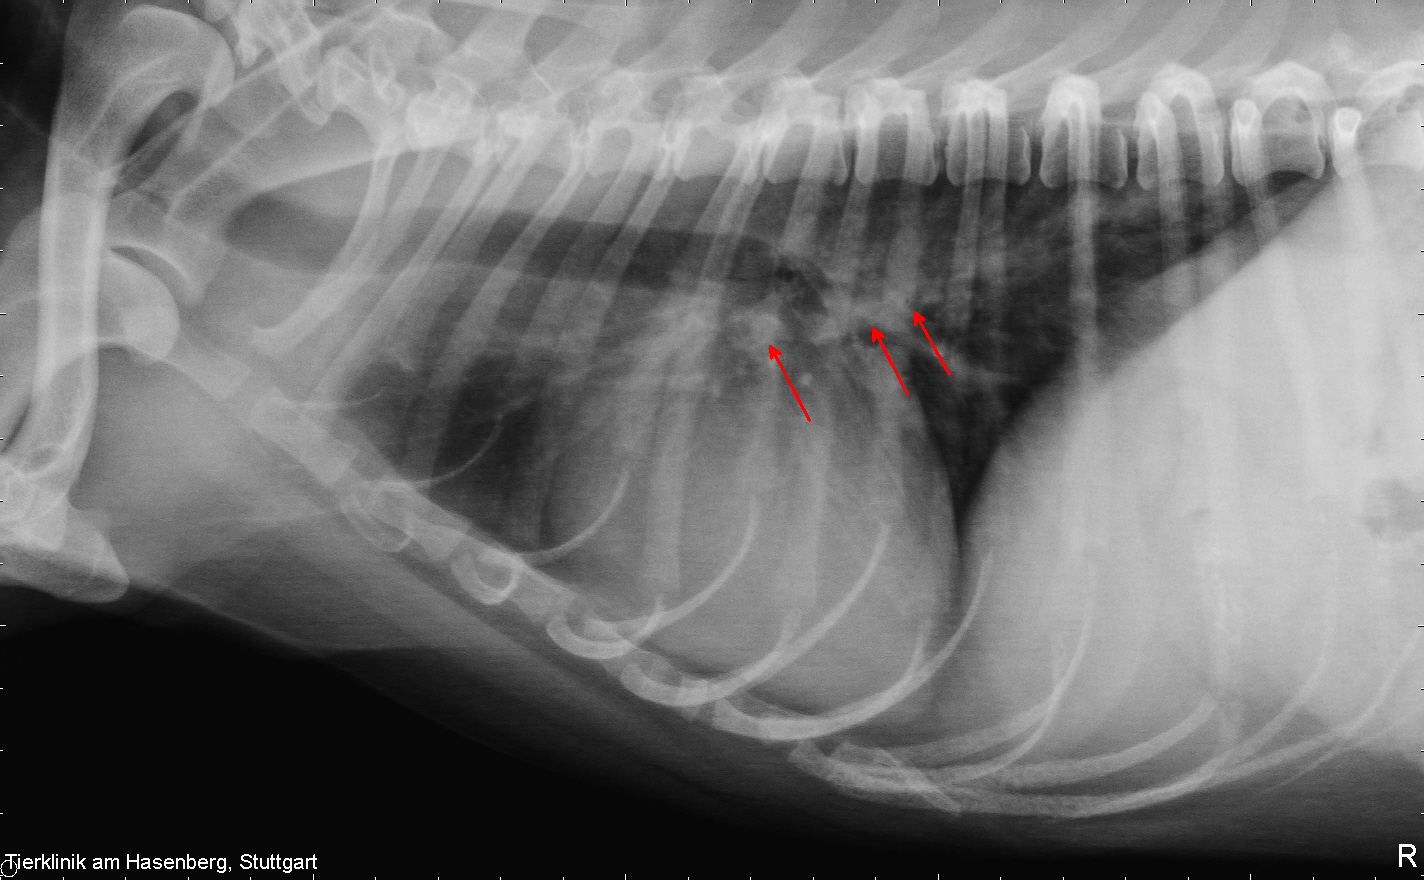

In der Sprechstunde zeigte sich Quax nun in stabilem Zustand. Beim Abhören des Brustraumes fielen ein Herznebengeräusch rechts mit einer Intensität 3/6 (Intensität wird in 6 Grade eingeteilt / Grad 3: moderate Lautstärke) und abnorme Atemnebengeräusch auf. Der Puls war kräftig und der Hund zeigte keine erneute Synkope während der Untersuchung. Wir fertigten Röntgenbilder des Brustraumes an, die eine leichte Herzvergrößerung mit Betonung des Rechtsherzens und wolkig-fleckige Verschattungen der Lunge im Hilusbereich und von da aus in den kaudalen Lungenlappen ziehend zeigten. In der Echokardiographie (Ultraschalluntersuchung des Herzens) ergab sich dann ein ungewöhnlicher Befund: die rechte Herzkammer war deutlich erweitert, und in ihr schwappte ein regelrechtes großes Knäul aus echogenen Doppellinienstrukturen im Blutfluss des Herzens hin und her. Die Pulmonalarterie, die aus der rechten Herzkammer in die Lunge führt, war erweitert, und auch da waren charakteristische Doppellinien zu sehen. Selbst im rechten Vorhof und bis in die davor liegende Vena Cava konnten sonographisch Doppellinien verfolgt werden. Dies war das typische Bild eines sogenannten Cavasyndroms, ausgelöst durch adulte Herzwürmer, die sich im Herzen aufhalten. Ein zusätzlich durchgeführter Herzwurm-Antigen-Test verlief dieses Mal positiv.